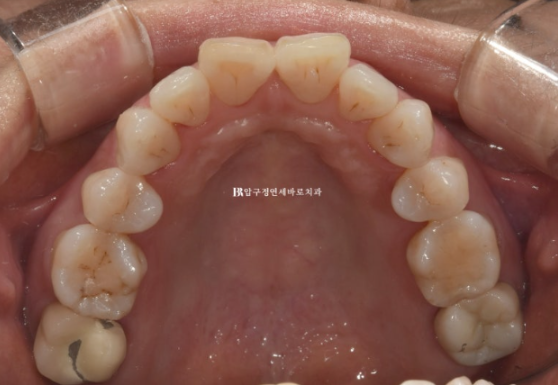

위 앞니 두개가 튀어나와있고 회전이 되어있습니다.

이 정도면 인비절라인 라이트로도 충분히 교정이 가능합니다.

인비절라인 라이트는 한 세트당 장치는 최대 14개까지 나옵니다.

환자분의 나이와 잇몸 상태를 고려하면 통상 교체 간격을 7일이 아닌 10일로 가져가는 것이 잇몸에 무리가 덜 갑니다.

첫 세트의 14개 장치를 다 끼는 시간은 140일 정도입니다.

배열이 가지런해졌고 소량의 치간삭제를 통해 블랙트라이앵글도 줄었습니다.

이 정도도 충분히 좋지만 100점 목표를 위해 추가장치 제작을 합니다.

추가장치를 2월부터 5월까지 3달간 10일씩 꼈고 마무리 했습니다.